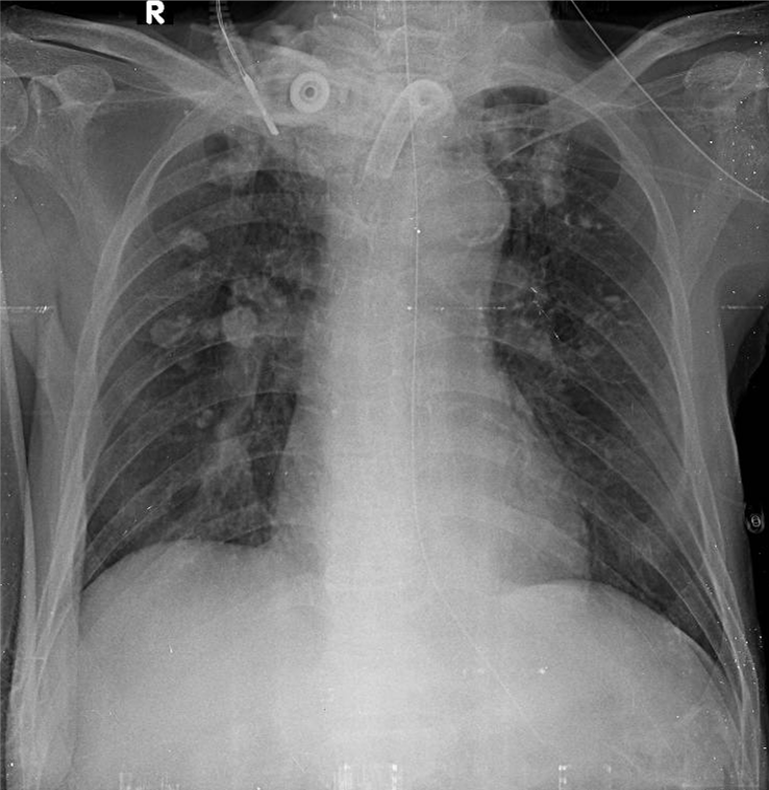

1-Đang mở khí quản ra da (canul) 2-Xơ vôi rải rác thùy trên hai phổi